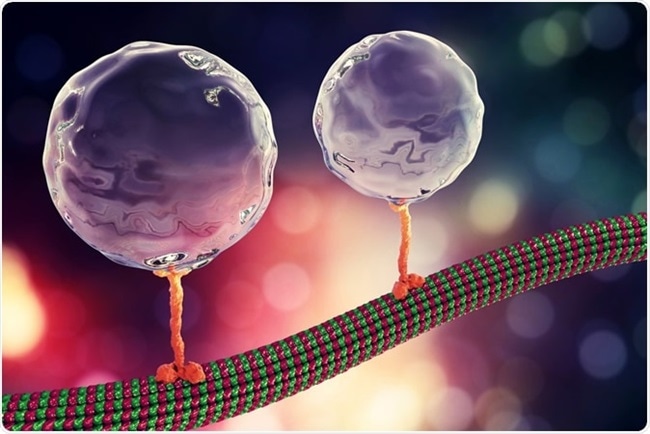

Immagine, il trasporto intracellulare, le proteine del motore di kinesin trasportano le molecole che si muovono attraverso i microtubuli. Illustrazione 3D. Credit.: Kateryna Kon / Shutterstock

Una cellula nervosa comprende un corpo cellulare e numerosi rami brevi chiamati dendriti. Ha anche una lunga proiezione chiamata assone che trasporta segnali lontano dal neurone. Le cellule nervose hanno anche minuscole tracce tubolari composte da microtubuli lungo cui il carico viene spostato da e verso i dendriti e gli assoni da un motore molecolare collegato, chiamato KIF1C.

Le cellule umane sintetizzano molti tipi di molecole motorie, chiamate kinesine e dineine che trasportano il carico verso le estremità opposte della cellula, ed entrambi i motori sono spesso presenti sui carichi in modo che possano cambiare direzione se i loro progressi sono ostacolati.